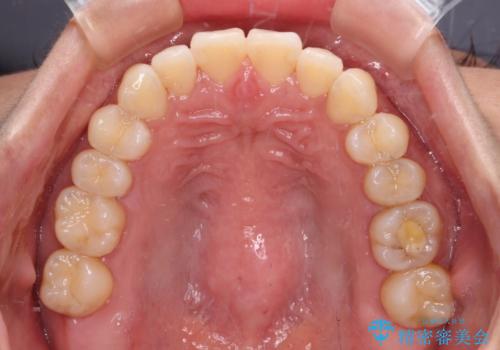

上顎前歯が捻れて前方に飛び出しており、下顎前歯もそれに沿うようにデコボコとなっていました。

IPR(歯と歯の間を削る処置)によりスペースを獲得して上下顎前歯のデコボコを改善し、飛び出している前歯が引っ込むように設定し、インビザラインにて矯正治療を行うこととしました。

装着時間を守ってくださったので、予定通りの期間で終えることができました。インビザライン特有の、奥歯の咬み合わせの問題もなく、しっかりと歯列を改善することができました。